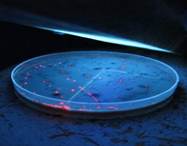

Las bacterias anaerobias pigmentadas (Porphyromonas y Prevotella) se identificaron por la formación de pigmento (Fig. 2). Para su diferenciación, se observaron también mediante fluorescencia bajo luz ultravioleta (360 nm) donde las colonias de P. gingivalis no fluorescen y las de P. intermedia si lo hacen (Fig. 3). En caso de dudas se realizó la identificación con pruebas bioquímicas para anaerobios a través del kit API®.

Colonias fluorescentes de Prevotella intermedia frente a luz ultravioleta